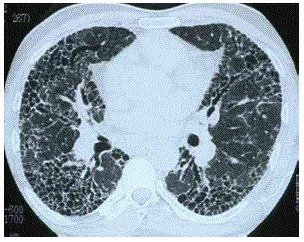

Dilatação da via aérea distal, com bronquiolectasias e bronquiolomucoceles, é a tradução de um padrão identifcado pela alta resolução no tórax.

Baseado na imagem disponibilizada, qual o seu diagnóstico?